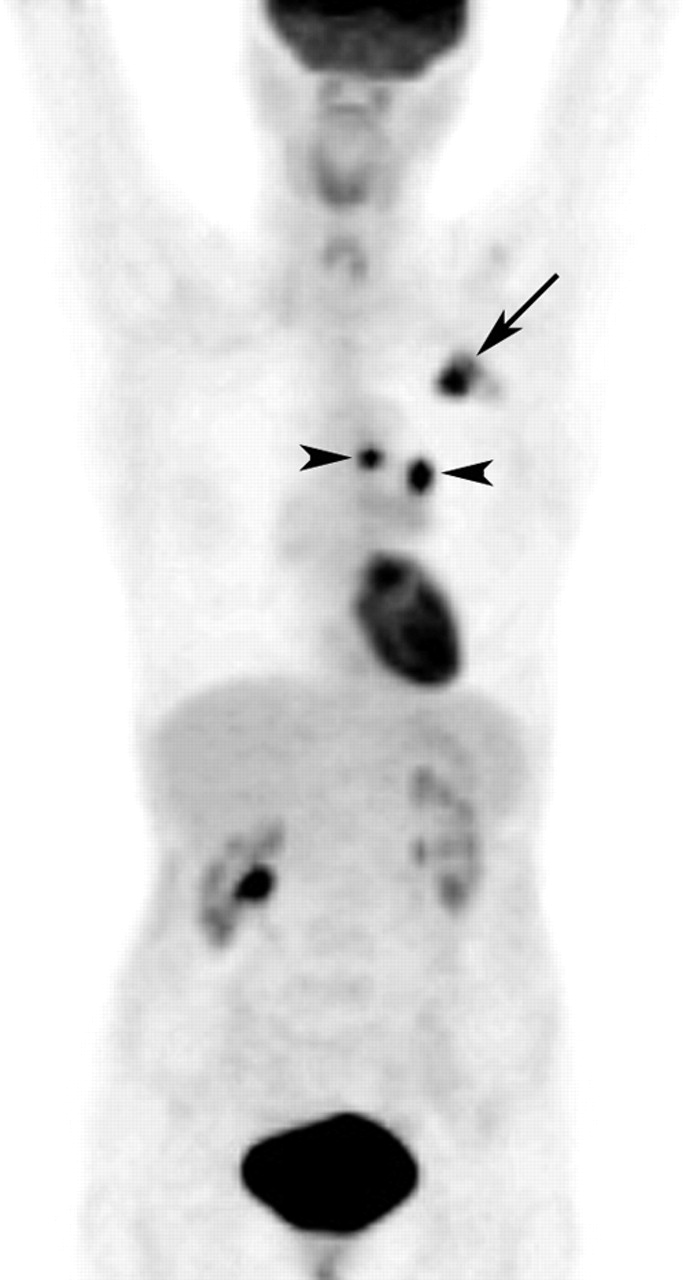

FDGPET scan identification of a primary lung carcinoma in a patient Does Pet Scan Cause Cancer Find out how big it is and whether it has spread (stage a cancer) show whether a lump is cancer or not;. A pet scan can help to: Many types of solid tumors. It’s crucial to understand that a positive pet scan does not exclusively indicate cancer. Younger patients who have chronic. This article explores the various. Pet scans must. Does Pet Scan Cause Cancer.